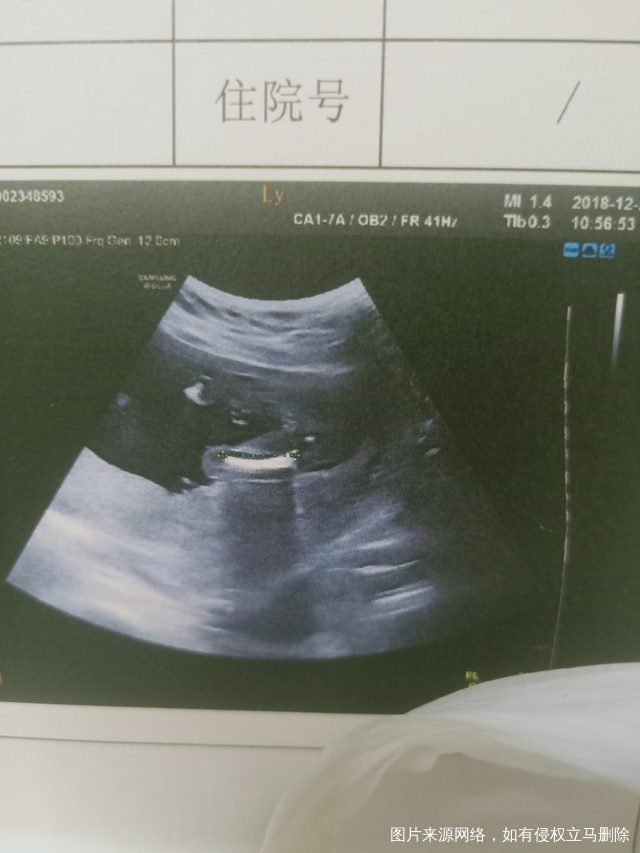

有大佬会看B超么~跪求帮看下这是屁股吗?

17周+3天拍的。是女宝吧?